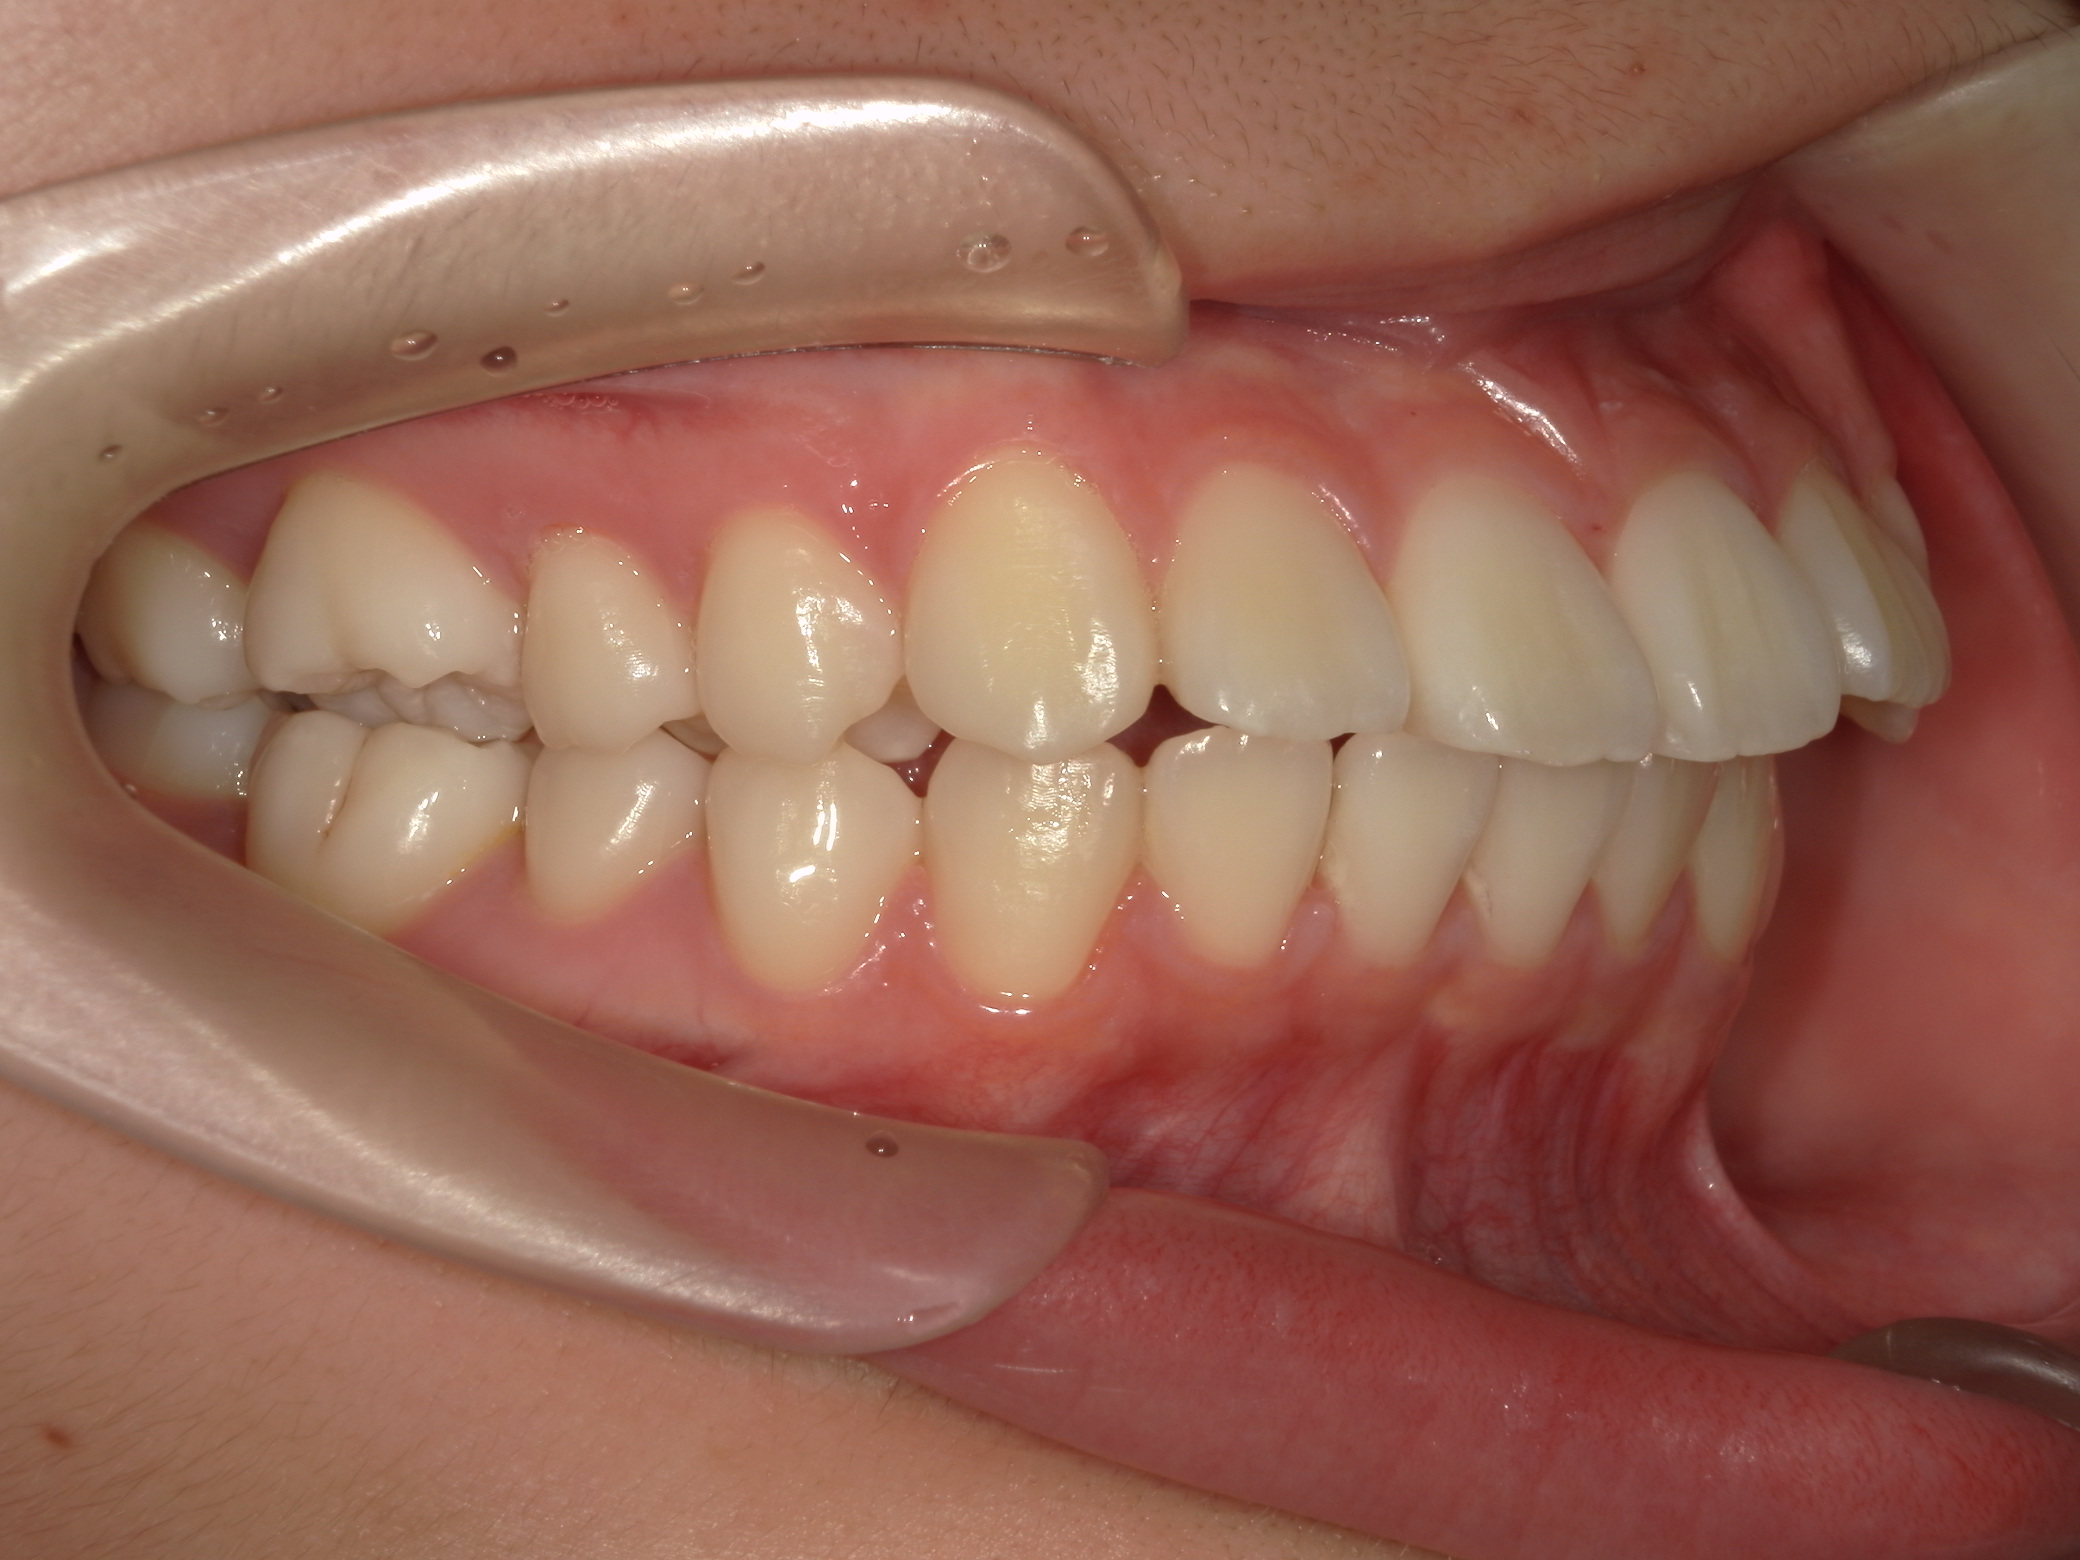

口元がすごく出ています。

斜め横から見ると立体的に出ているのが判ります。

笑うと歯がすごく出ています。